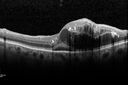

Macroaneurysm - Resolved without treatment416 views87 year old female with vision loss OD. Initial FA showed no leakage so no treatment was done and the fluid absorbed over 4 months. Initial VA 20/100, Final VA 20/80

Macroaneurysm - Resolved without treatment402 views87 year old female with vision loss OD. Initial FA showed no leakage so no treatment was done and the fluid absorbed over 4 months. Initial VA 20/100, Final VA 20/80

Macroaneurysm - Resolved without treatment400 views87 year old female with vision loss OD. Initial FA showed no leakage so no treatment was done and the fluid absorbed over 4 months. Initial VA 20/100, Final VA 20/80

Macroaneurysm - Resolved without treatment391 views87 year old female with vision loss OD. Initial FA showed no leakage so no treatment was done and the fluid absorbed over 4 months. Initial VA 20/100, Final VA 20/80

Macroaneurysm - Resolved without treatment390 views87 year old female with vision loss OD. Initial FA showed no leakage so no treatment was done and the fluid absorbed over 4 months. Initial VA 20/100, Final VA 20/80

Macroaneurysm - Resolved without treatment387 views87 year old female with vision loss OD. Initial FA showed no leakage so no treatment was done and the fluid absorbed over 4 months. Initial VA 20/100, Final VA 20/80

Macroaneurysm - Resolved without treatment380 views87 year old female with vision loss OD. Initial FA showed no leakage so no treatment was done and the fluid absorbed over 4 months. Initial VA 20/100, Final VA 20/80

Macroaneurysm - Resolved without treatment374 views87 year old female with vision loss OD. Initial FA showed no leakage so no treatment was done and the fluid absorbed over 4 months. Initial VA 20/100, Final VA 20/80

Macroaneurysm - Resolved without treatment371 views87 year old female with vision loss OD. Initial FA showed no leakage so no treatment was done and the fluid absorbed over 4 months. Initial VA 20/100, Final VA 20/80

Macroaneurysm - Resolved without treatment369 views87 year old female with vision loss OD. Initial FA showed no leakage so no treatment was done and the fluid absorbed over 4 months. Initial VA 20/100, Final VA 20/80

Macroaneurysm - Resolved without treatment367 views87 year old female with vision loss OD. Initial FA showed no leakage so no treatment was done and the fluid absorbed over 4 months. Initial VA 20/100, Final VA 20/80

Macroaneurysm - Resolved without treatment362 views87 year old female with vision loss OD. Initial FA showed no leakage so no treatment was done and the fluid absorbed over 4 months. Initial VA 20/100, Final VA 20/80

Macroaneurysm - Resolved without treatment361 views87 year old female with vision loss OD. Initial FA showed no leakage so no treatment was done and the fluid absorbed over 4 months. Initial VA 20/100, Final VA 20/80

Macroaneurysm - Resolved without treatment358 views87 year old female with vision loss OD. Initial FA showed no leakage so no treatment was done and the fluid absorbed over 4 months. Initial VA 20/100, Final VA 20/80

Macroaneurysm - Resolved without treatment357 views87 year old female with vision loss OD. Initial FA showed no leakage so no treatment was done and the fluid absorbed over 4 months. Initial VA 20/100, Final VA 20/80

Macroaneurysm - Resolved without treatment355 views87 year old female with vision loss OD. Initial FA showed no leakage so no treatment was done and the fluid absorbed over 4 months. Initial VA 20/100, Final VA 20/80

Macroaneurysm - Resolved without treatment353 views87 year old female with vision loss OD. Initial FA showed no leakage so no treatment was done and the fluid absorbed over 4 months. Initial VA 20/100, Final VA 20/80

Macroaneurysm - Resolved without treatment349 views87 year old female with vision loss OD. Initial FA showed no leakage so no treatment was done and the fluid absorbed over 4 months. Initial VA 20/100, Final VA 20/80